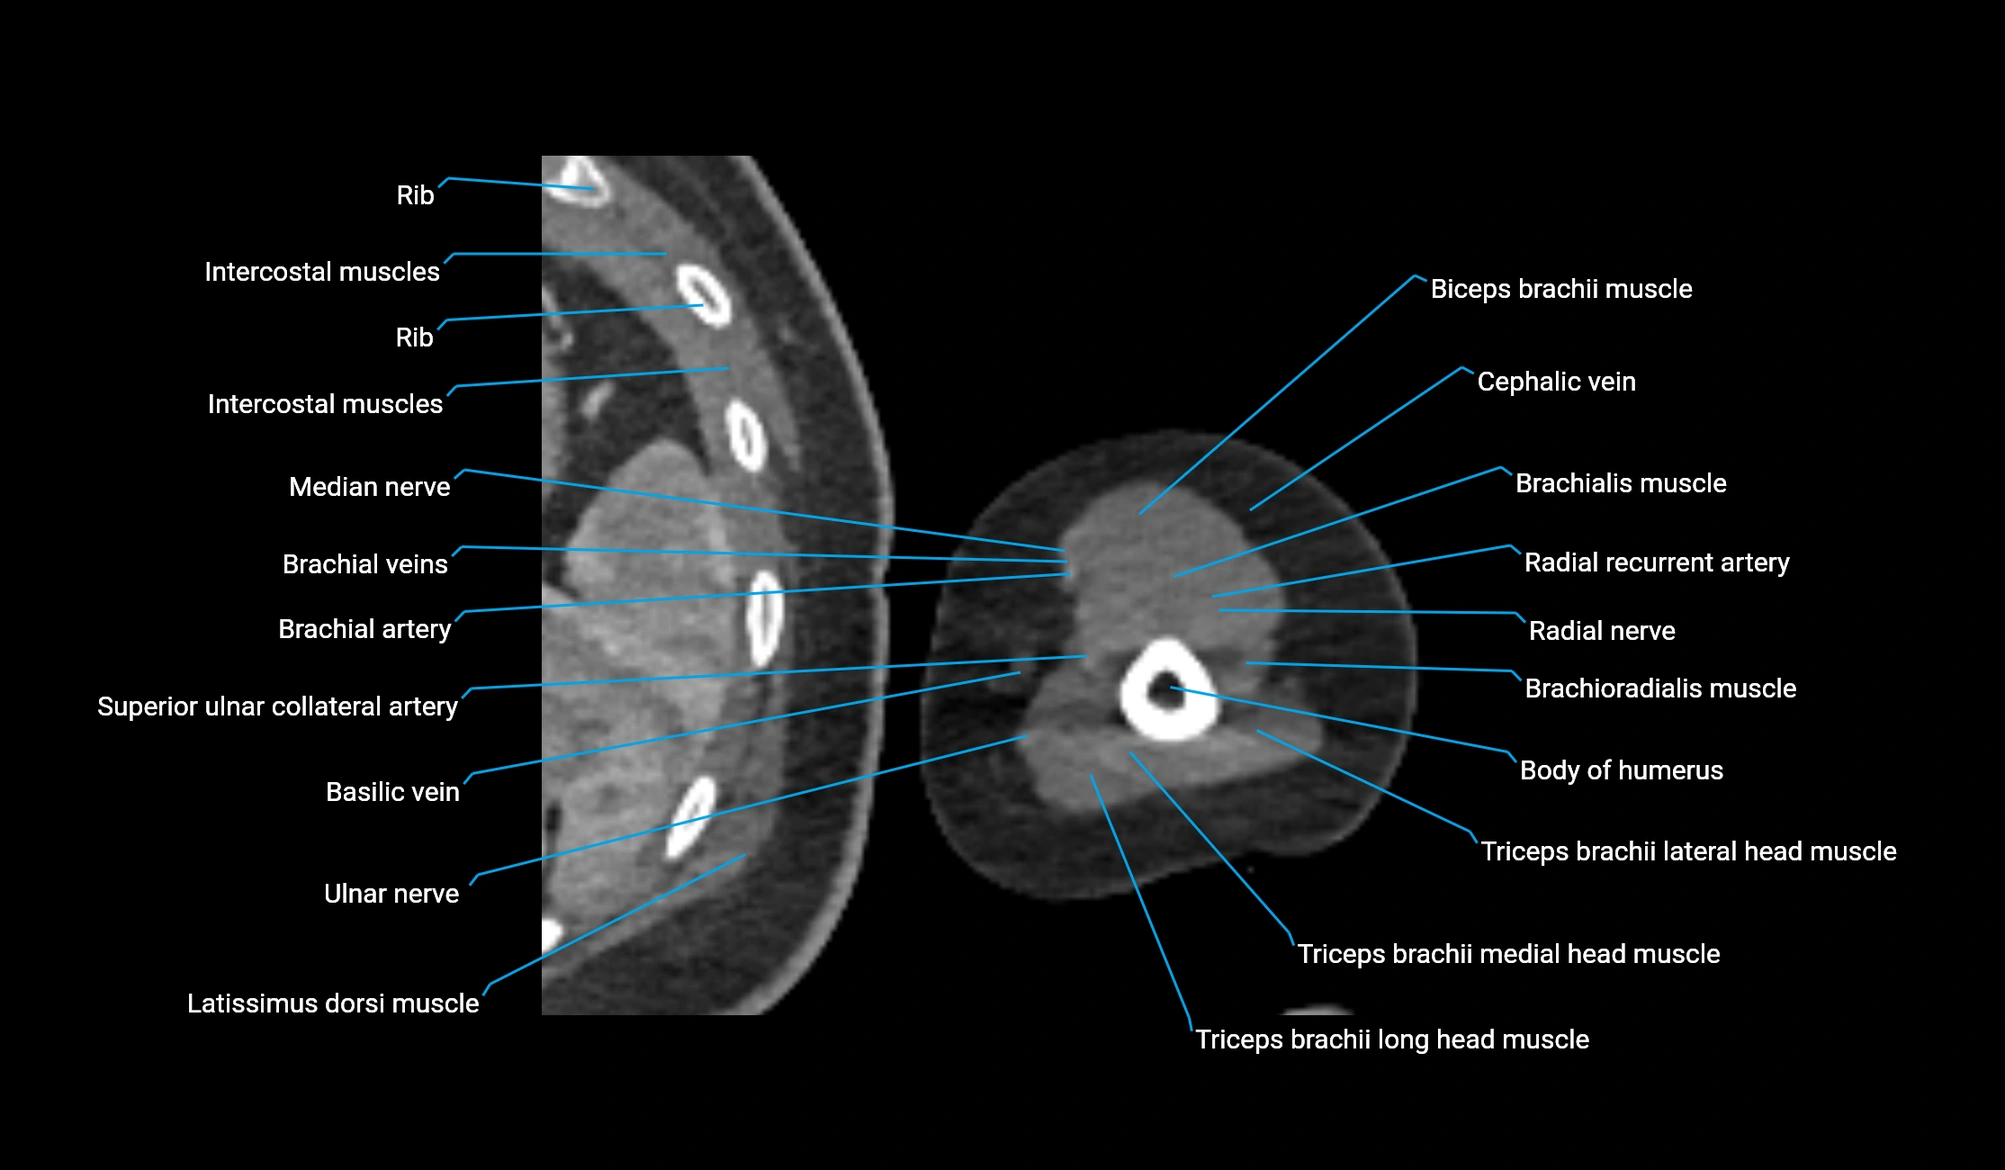

CT image